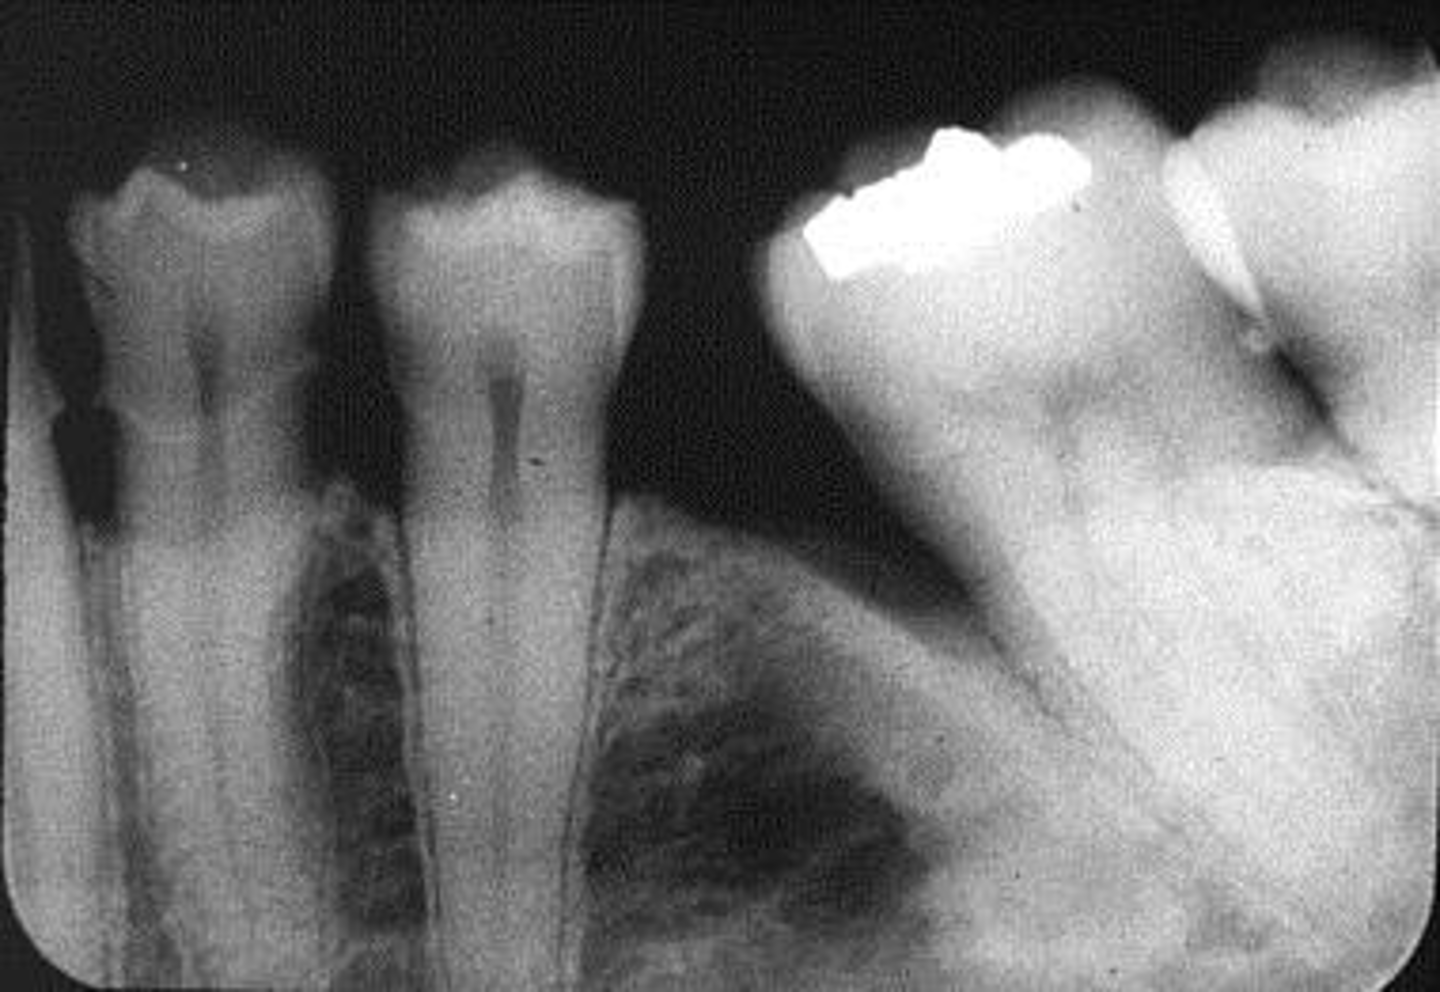

Horizontal angulation, no apices show, vertical angulation

What is this error?